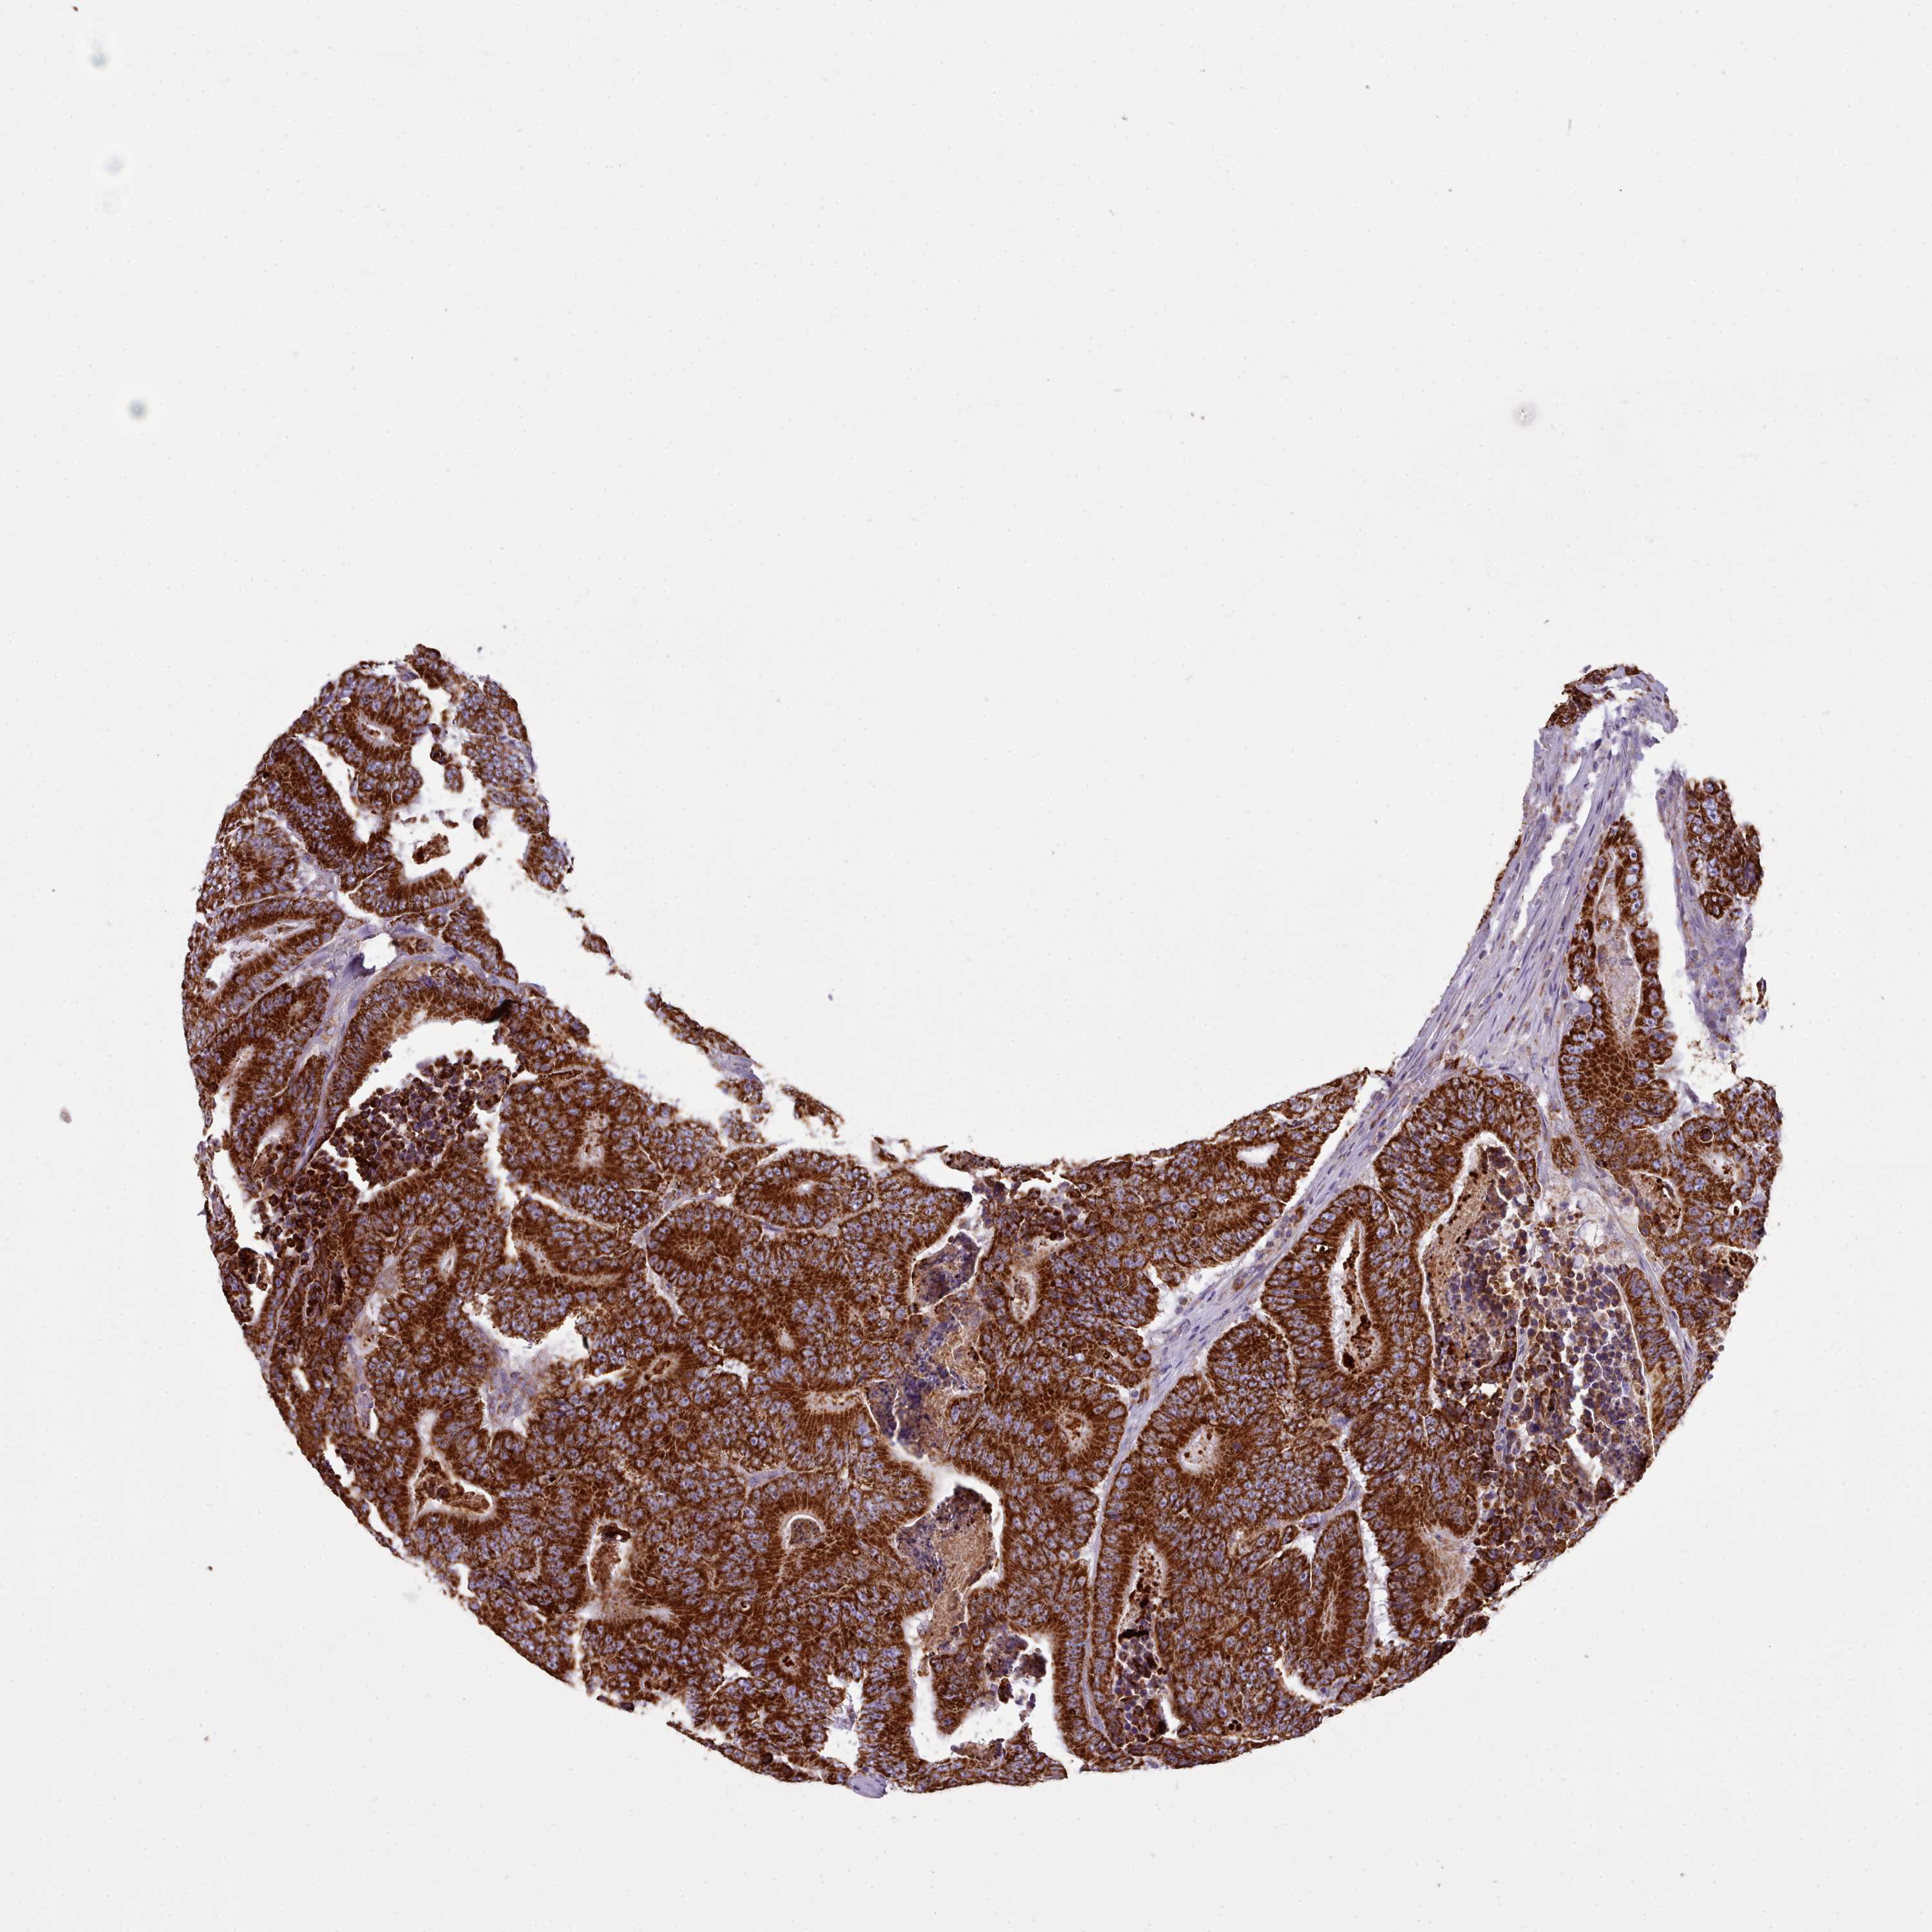

CANCER COLORECTAL CANCER Show tissue menu

Colorectal cancer

Human cancer

Colon adenocarcinoma